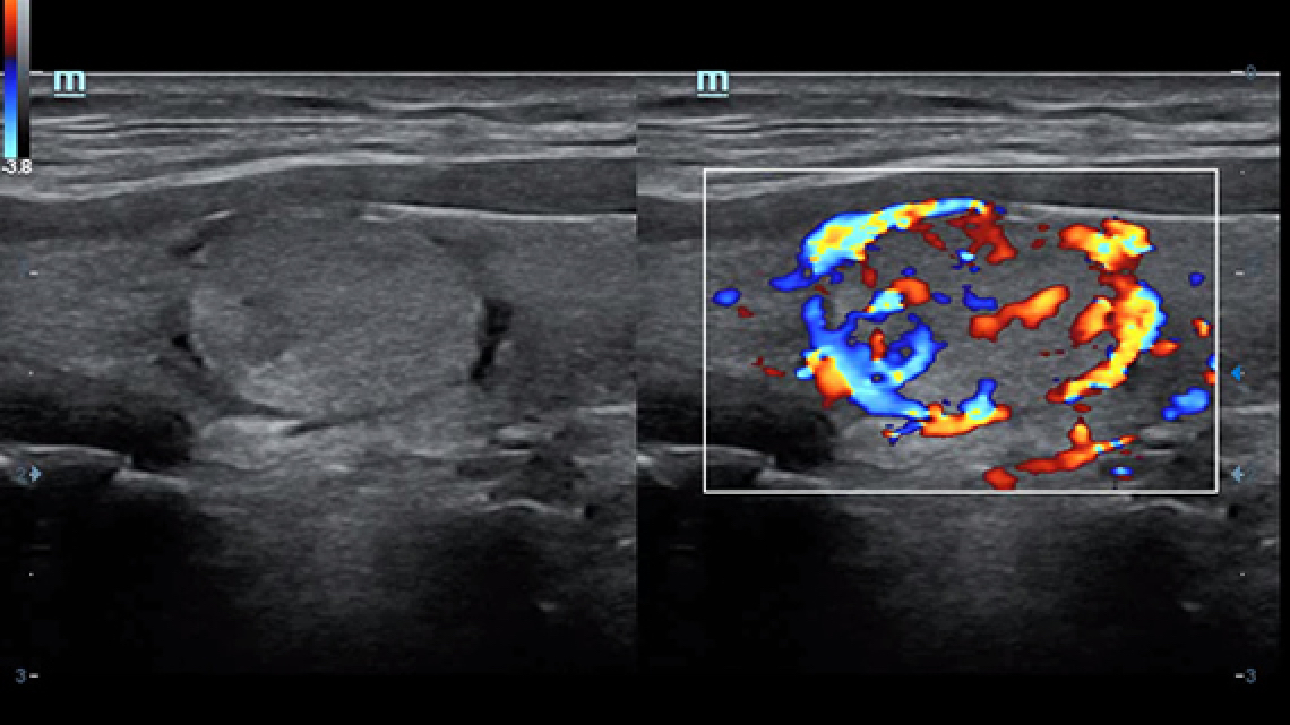

Clinical Images